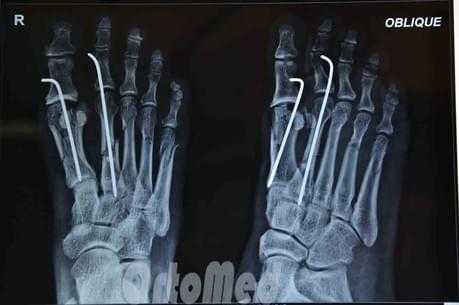

Чрескожная фиксация спицами

Была популярна на протяжении многих лет и продолжает оставаться одним из самых популярных методов в международном масштабе.

Сначала врач закрыто устраняет смещение отломков, затем через отломки в определенных (учитывая характер перелома) направлениях просверливаются спицы.

Плюсы: малая травматичность, быстрота, легкость, дешевизна, отсутствие разреза и как следствие послеоперационного рубца.

Минусы: концы спиц остаются над кожей, для того чтобы спицу можно было удалить после срастания перелома; риск инфицирования раны и проникновение инфекции в область перелома; длительное ношение гипсовой повязки 1 месяц; неудобства в повседневной жизни.